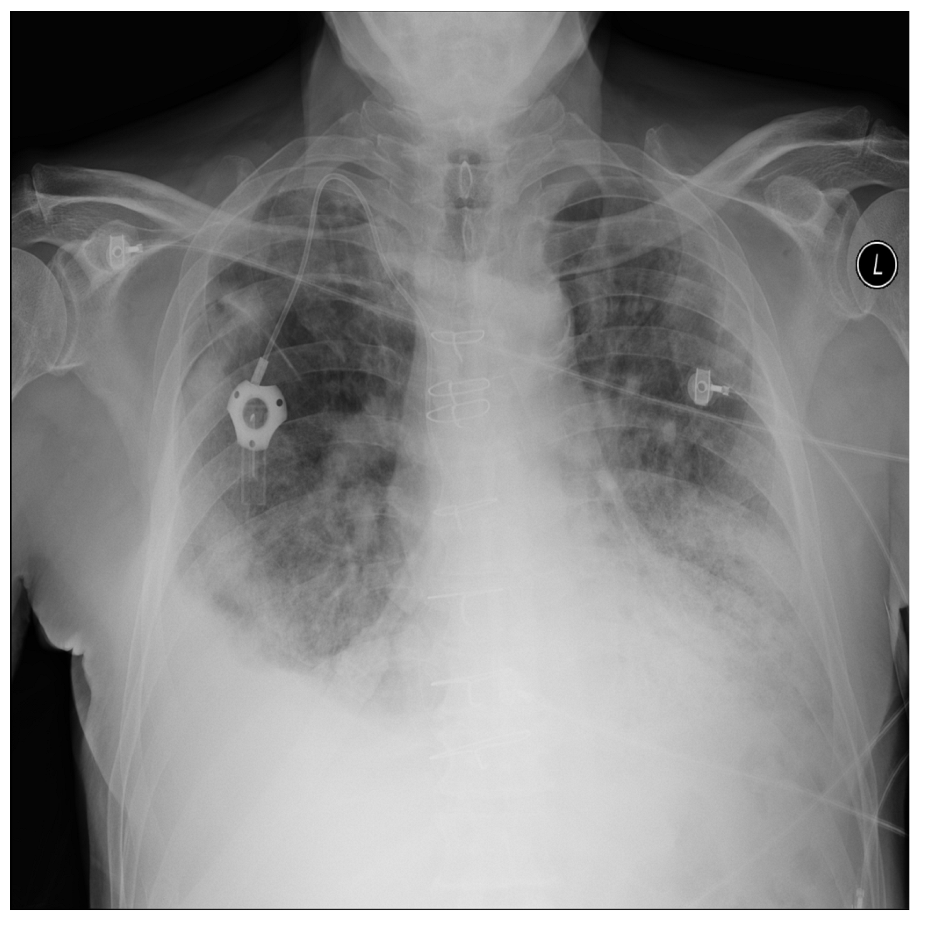

Figure 12 and Figure 13 demonstrate a pneumonia sample and a normal sample from the synthetic-covid-cxr dataset.

Figure 12. Pneumonia sample: synthetic-covid-cxr.

Applsci 13 00454 g012

Figure 13. Normal sample: synthetic-covid-cxr.

Applsci 13 00454 g013